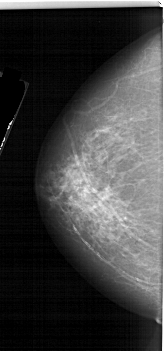

A_1252_1.LEFT_CC

LEFT_CC LINES 5956 PIXELS_PER_LINE 2776 BITS_PER_PIXEL 12 RESOLUTION 43.5 NON_OVERLAY